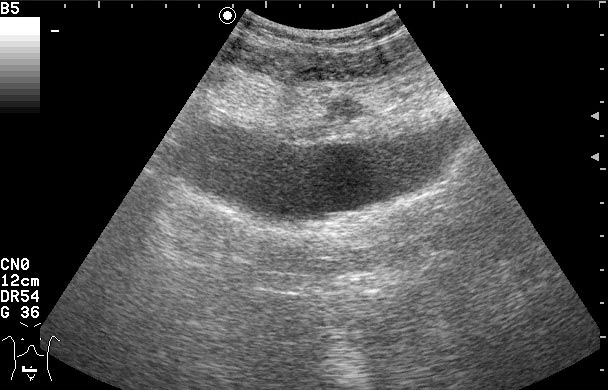

Женщина 42 лет с болями внизу живота, дизурическими явлениями, повышением температуры.

Сонограммы мочевого пузыря

Похоже на опухоль, но по анамнезу я больше склоняюсь к воспалению урахуса!

Согласна с первым постом-возможно нагноение урахуса(и клиника подходит)

Пациентке была выполнена биопсия образования, назначена антибактериальная и противовоспалительная терапия.

Клиническое выздоровление через 2 недели. Сонограммы мочевого пузыря через 6 недель: